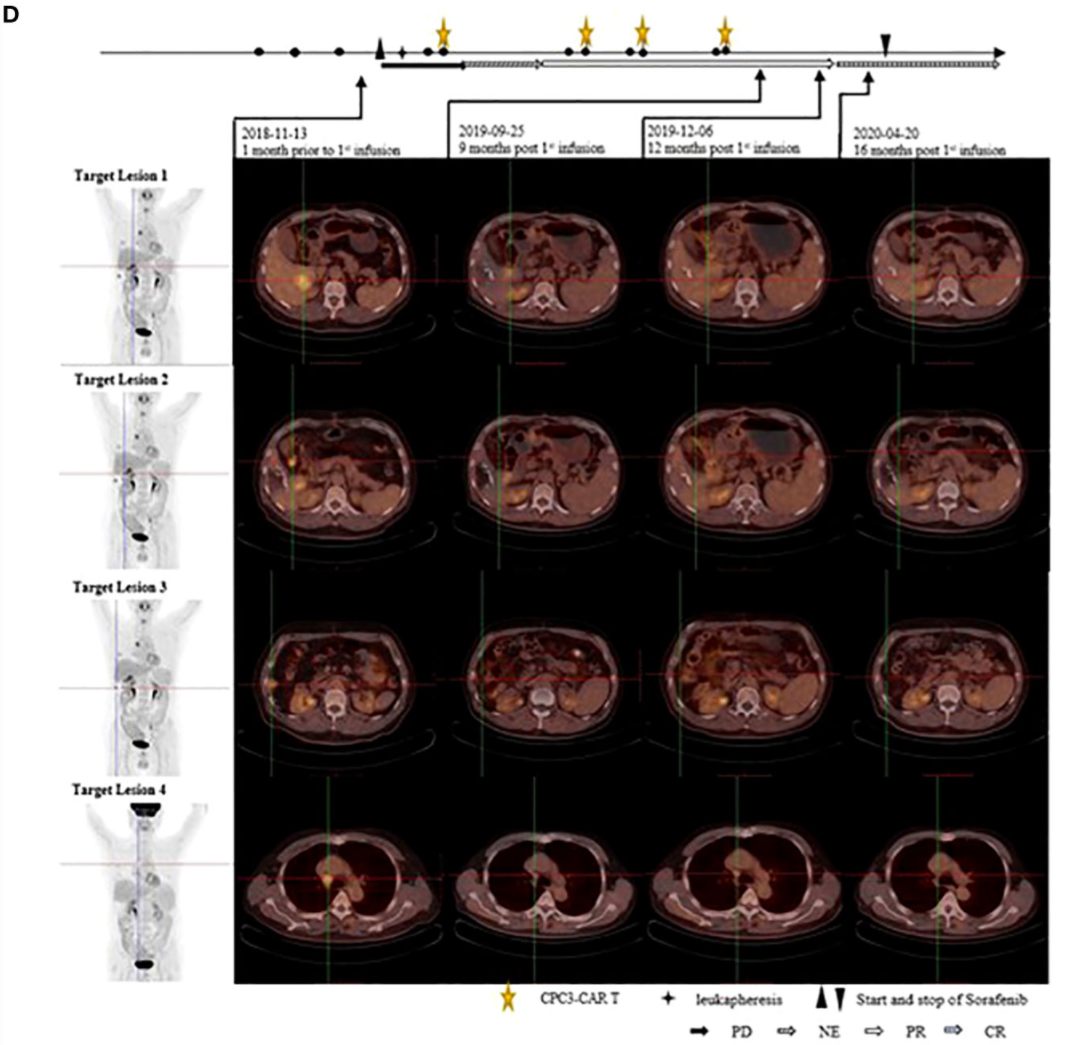

如首个针对GPC3的 实体瘤CAR-T 细胞疗法,成功为T细胞装载了能特异性识别GPC3癌细胞的“导航头”,使T细胞成为精准杀伤的“特种兵”。其中GPC3是一种正常组织中几乎未见表达,但在70-80%的肝细胞癌中表达的理想特异靶标。

国内一位晚期肝癌患者,接受40亿(4×109) 个GPC3 CAR-T细胞治疗后1年,全身病灶消失,达到完全缓解,并且36个月没有进展,在第一次输注后保持完全缓解状态超过24个月!